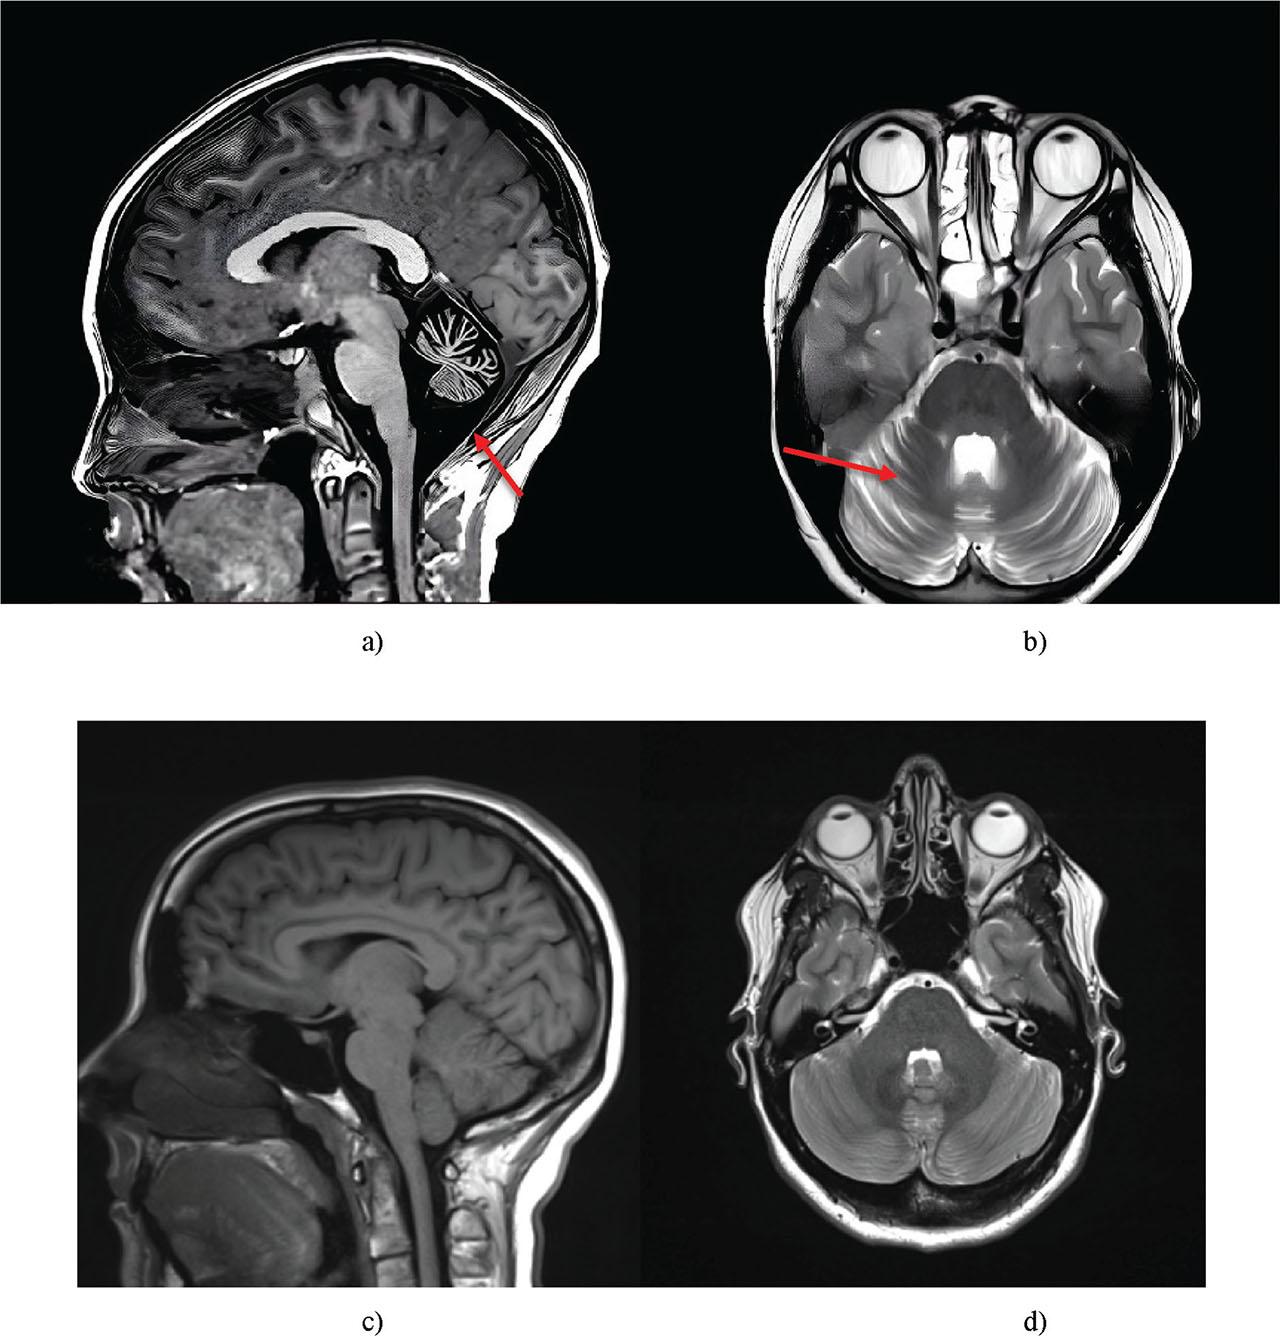

| Brain MRI | Identification of cerebellar atrophy, enlargement of the cisterna magna |